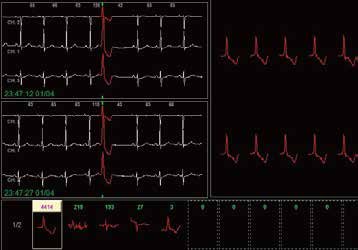

Die Edan Holter Systeme (SE-2003/2012 als auch SE-2003A/2012A) bieten Ihnen einen leichten und kompakten digitalen Rekorder sowie eine schnelle und leistungsstarke Analysesoftware. Optimierter Workflow und einstellbare Parameter zielen darauf ab, Ihre unterschiedlichen klinischen Anforderungen zu erfüllen

Holter Recorder

Holter Software